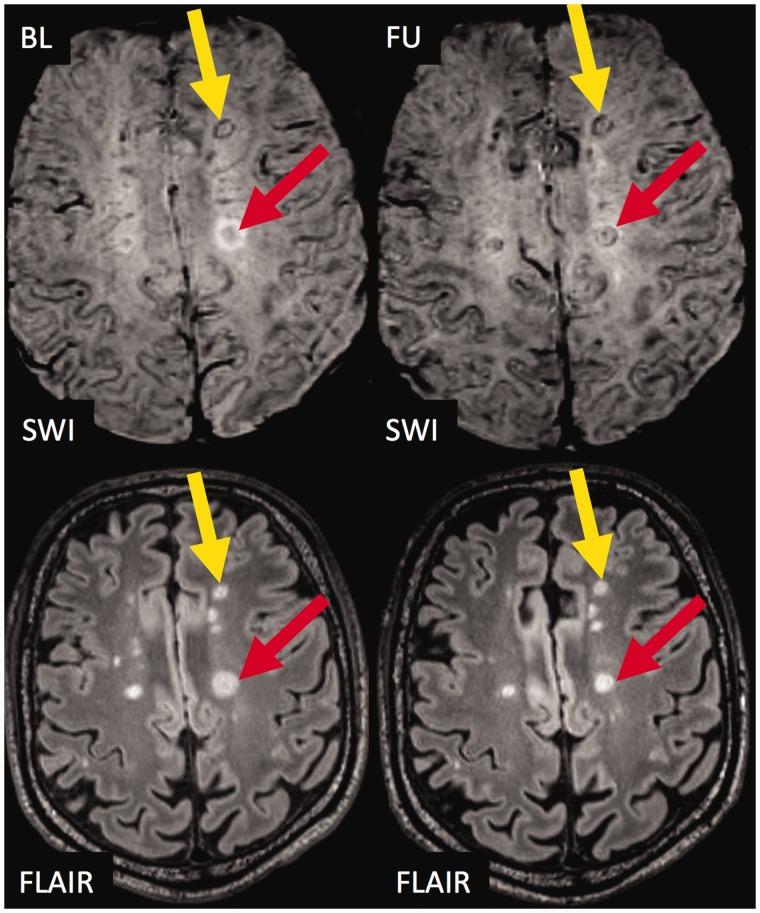

Brain lesions with a hypointense ring or core were described in multiple sclerosis on susceptibility weighted imaging.

The purpose of this study was to study the evolution and prognostic relevance of susceptibility weighted imaging hypointense lesions in clinically isolated syndrome and early multiple sclerosis.

Sixty-six early multiple sclerosis and clinically isolated syndrome patients were followed over a median period of 2.9 years (range 1.6-4.6 years) and underwent 3T magnetic resonance imaging including 3D susceptibility weighted imaging and T2-weighted fluid-attenuated inversion recovery. We assessed the presence of susceptibility weighted imaging hypointense core or ring lesions, and Expanded Disability Status Scale at baseline and follow-up.

Of 611 lesions at baseline, 64 (10.5%) had a susceptibility weighted imaging hypointense core, and 28 (4.6%) had a susceptibility weighted imaging hypointense ring. Hypointense ring lesions were larger ( < 0.001) and more T1w hypointense ( = 0.002) than others. During follow-up, hypointense core lesions became susceptibility weighted imaging isointense (52 lesions, 81%); few developed into hypointense ring lesions (two lesions, 3%). Hypointense ring lesions did not shrink on T2-weighted fluid-attenuated inversion recovery images ( = 0.077, trend towards more enlargement compared to others), while hypointense core lesions more often shrunk in comparison to lesions without a hypointense core ( = 0.002). The number of susceptibility weighted imaging hypointense ring lesions at baseline correlated with Expanded Disability Status Scale progression at follow-up ( = 0.021, R = 0.289).

In our cohort of patients with clinically isolated syndrome or early multiple sclerosis, susceptibility weighted imaging hypointense ring lesions were only rarely detectable, but did not shrink and were associated with future disability progression.

在多系统硬化症的磁敏感加权成像中发现了具有低信号环或核心的脑病变。

本研究旨在探讨临床孤立综合征和早期多系统硬化症中磁敏感加权成像低信号病变的演变及其与预后的相关性。

对66例早期多系统硬化症和临床孤立综合征患者进行了为期2.9年(范围1.6 - 4.6年)的随访,并接受了3T磁共振成像检查,包括三维磁敏感加权成像和T2加权液体衰减反转恢复序列成像。我们评估了磁敏感加权成像低信号核心或环病变的存在情况,以及基线和随访时的扩展残疾状态量表。

在基线时的611个病变中,64个(10.5%)有磁敏感加权成像低信号核心,28个(4.6%)有磁敏感加权成像低信号环。低信号环病变比其他病变更大(<0.001)且T1加权像上低信号更明显(=0.002)。在随访期间,低信号核心病变在磁敏感加权成像上变为等信号(52个病变,81%);少数发展为低信号环病变(2个病变,3%)。低信号环病变在T2加权液体衰减反转恢复序列图像上没有缩小(=0.077,与其他病变相比有增大趋势),而低信号核心病变与无低信号核心的病变相比更常缩小(=0.002)。基线时磁敏感加权成像低信号环病变的数量与随访时扩展残疾状态量表的进展相关(=0.021,R = 0.